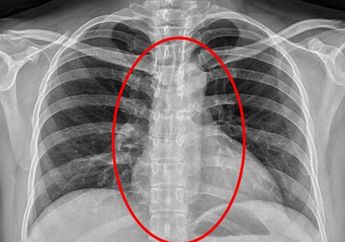

8 Tahun yang lalu - Dokter menemukan sebuah kondom dalam saluran pencernaan seorang wanita setelah dilakukan rontgen.